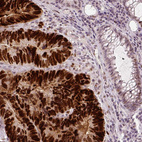

Immunohistochemistry analysis in human skin and skeletal muscle tissues using AMAb90956 antibody. Corresponding p53 RNA-seq data are presented for the same tissues.